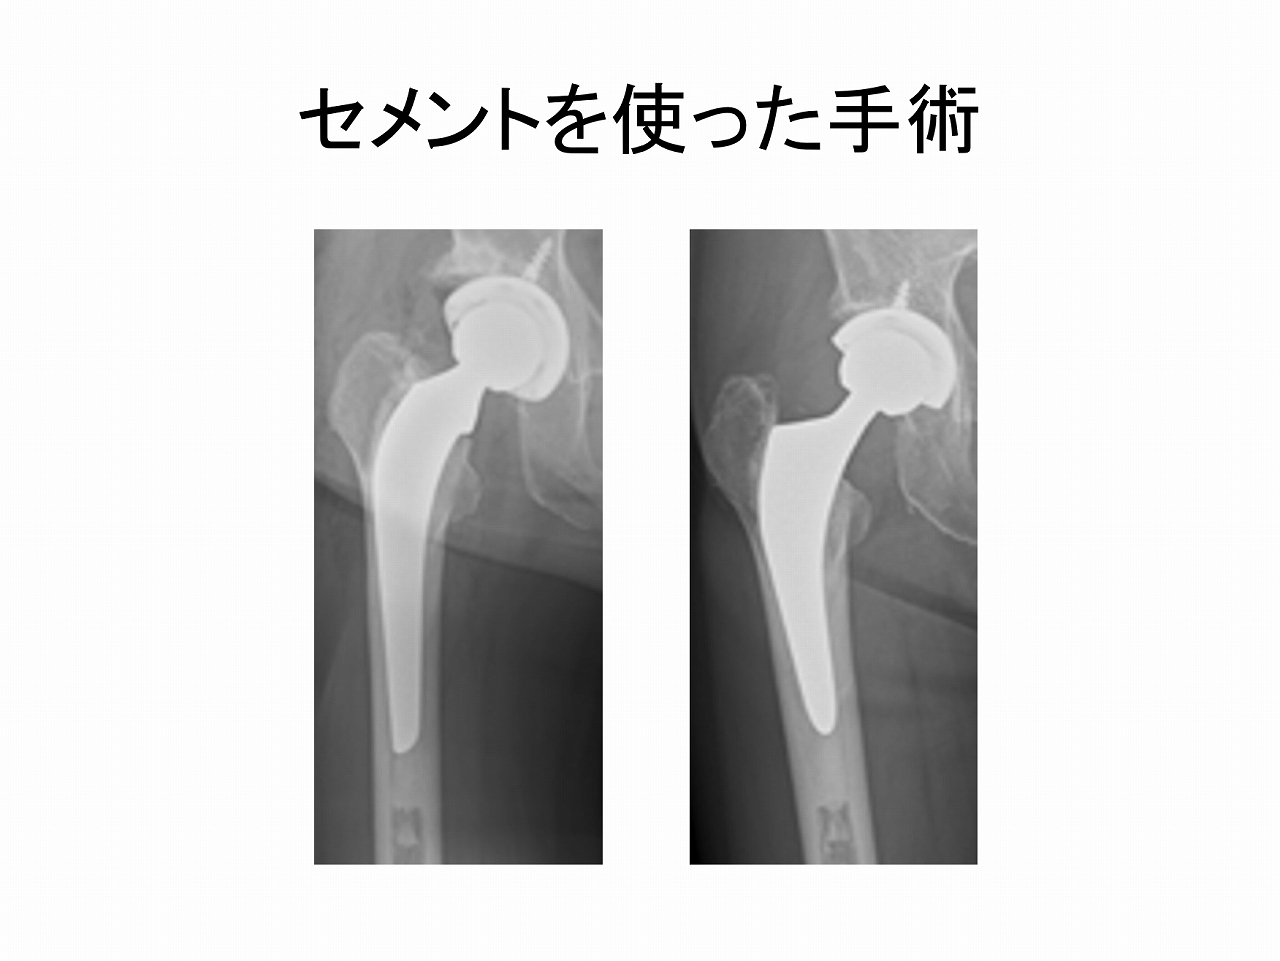

特に骨が弱くなっている(骨粗鬆症)の方は、骨折の危険性が高いです。その場合セメントを使った手術のほうが安全です。